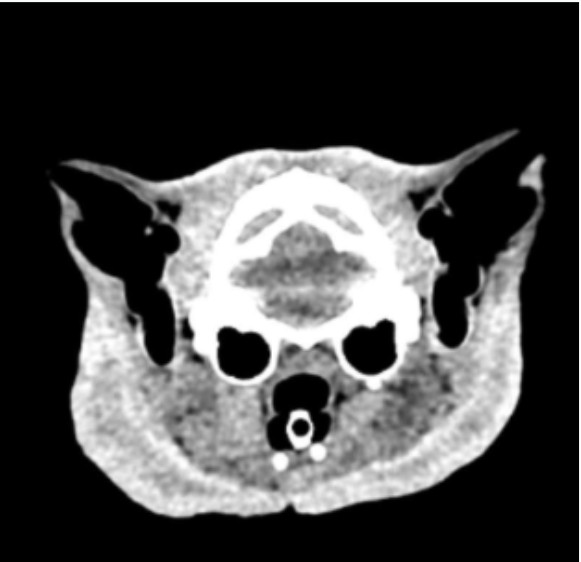

Rusty vivait dehors depuis longtemps. Nourri et surveillé par une habitante, il menait sa vie de chat errant, discret mais présent. Puis un jour, tout a basculé. En venant le nourrir, elle l’a retrouvé gravement blessé. Son visage était touché, son état inquiétant. Pris en charge en urgence, Rusty a rapidement été examiné. Le diagnostic est lourd : sept fractures au niveau du visage, une rhinite, plusieurs lésions. Une intervention chirurgicale s’impose sans attendre. Dans le même temps, les tests révèlent qu’il est positif au FIV.